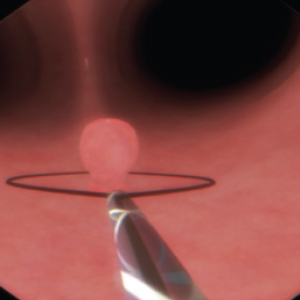

Real-feel surgical simulation. Diagnostic and surgical skills in Endoscopy

EndoVision sets the standard in simulation for hands-on-training in endoscopic procedures. Allowing trainees realistic and safe clinical experiences

EndoVision offers exposure to an extensive library of modules and patient cases to challenge diagnostic and psychomotor skills in preparation for real presentations.

High-precision no-lag instrument tracking system provides accurate, smooth response for all your actions.